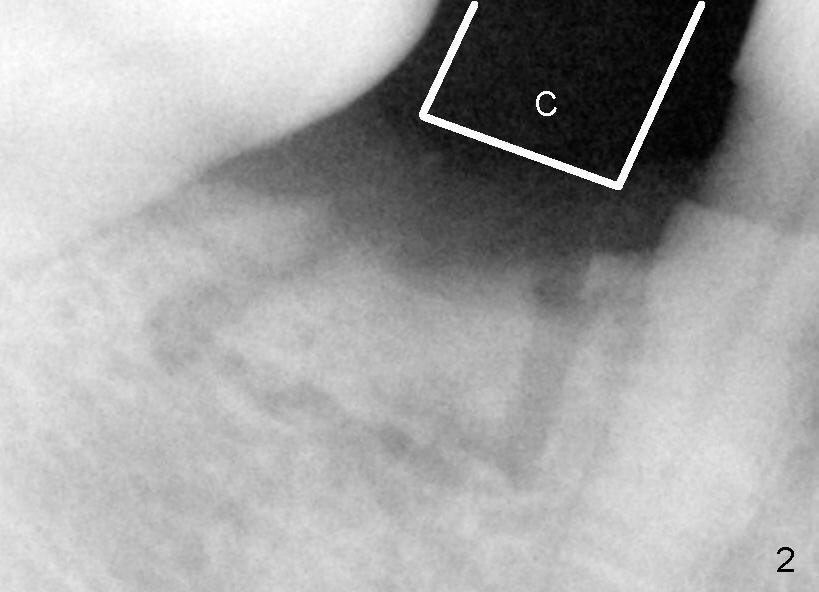

The phobic patient returns 5 weeks after the first surgery. Fig.1, 2 are taken in the first surgery. Fig.2 is used to show that the curved chisel (C) used for the 2nd surgery is wider than the superior bone cut. It appears that the buccal plate does not move when the chisel is applied.